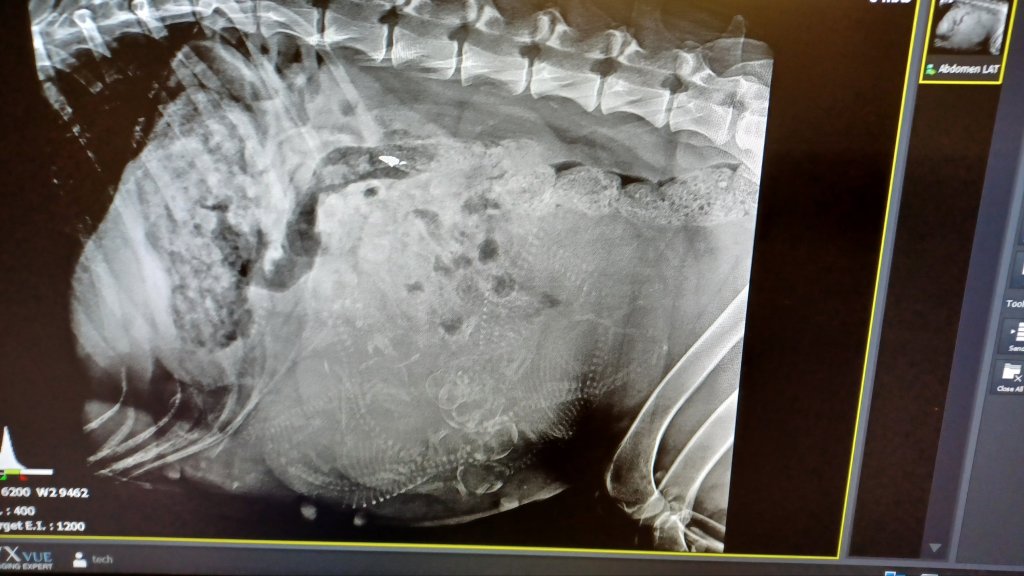

See See is going to have 9 or 10 puppies per Dr. Miller at Crossroads West Veterinary Center! When there are that many, it really is hard to tell. See See seems fine with all the fuss! Due date is approximately January 10, 2024